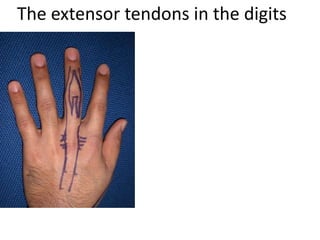

- It describes flexor tendon zones, extensor compartments, and pulley system anatomy.